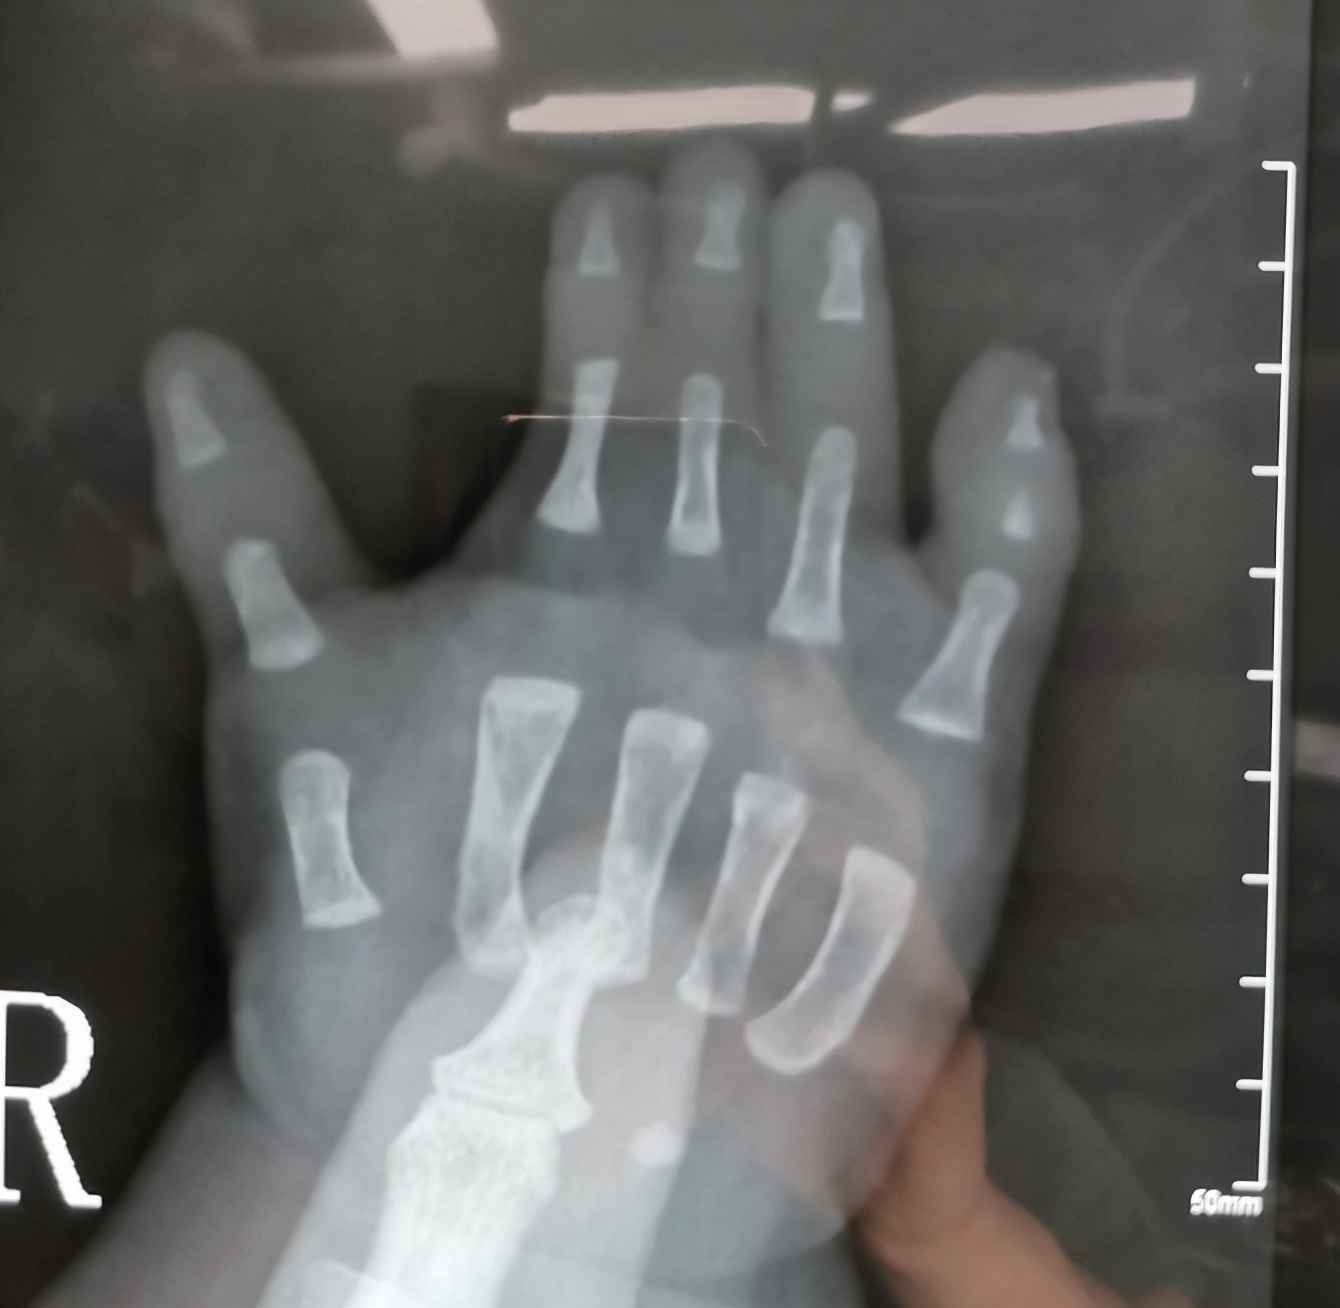

病例7:看到这样的手之后,很多人的第一反应就是怎么只有三根手指,能不能通过手术把三根手指变成五根。其实对于这个孩子的情况,还是要先把并指分开,分开之后可以考虑四根手指,因为通过对比X线片子,我们发现只有三根手指的这个手的第二根手指的指骨和掌骨都比好的那个手指的指骨和掌骨粗,这就意味着这是一个完全的复杂并指。

右手x线

左手x线

如果家长有需求,我们可以给这个孩子进行第二次分指,把三根手指变成四根,分指之后粗细有一定的保障,但是五根手指的可能性不大,哪怕从脚上移植,外观、功能和协调性可能都达不到我们想要的效果,所以四根手指可以探讨,五根意义不大。